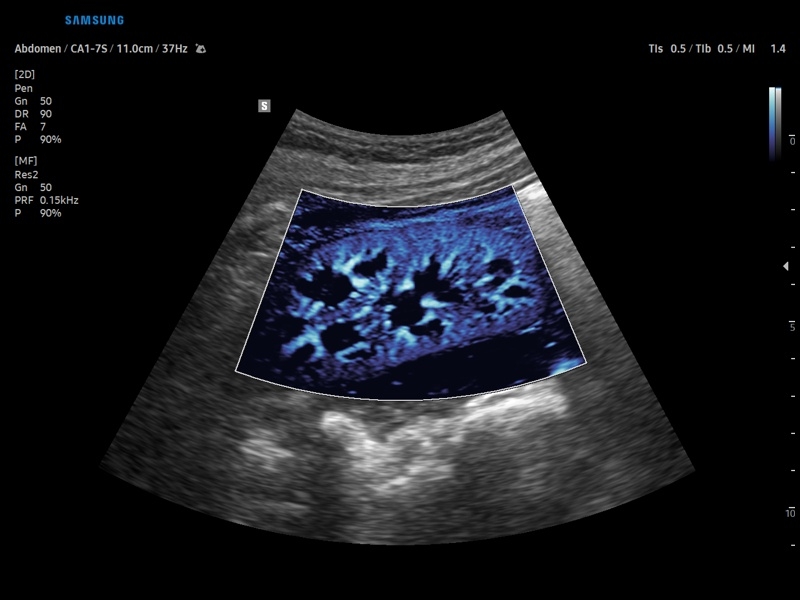

• Цветной, энергетический и направленный энергетический допплер

• Технологии визуализации: MV Flow, LumiFlow, SEE Stream, Panoramic

• Модуль MV-Flow – программа (режим), позволяющая визуализировать кровоток в микроциркуляторном русле с высоким разрешением без использования контраста.

• Модуль LumiFlow – программа отображения кровотока с объемной графикой для лучшего понимания архитектоники сосудистого русла.

• Модуль MV-Flow - программа (режим), позволяющая визуализировать кровоток в микроциркуляторном русле с высоким разрешением без использования контраста.